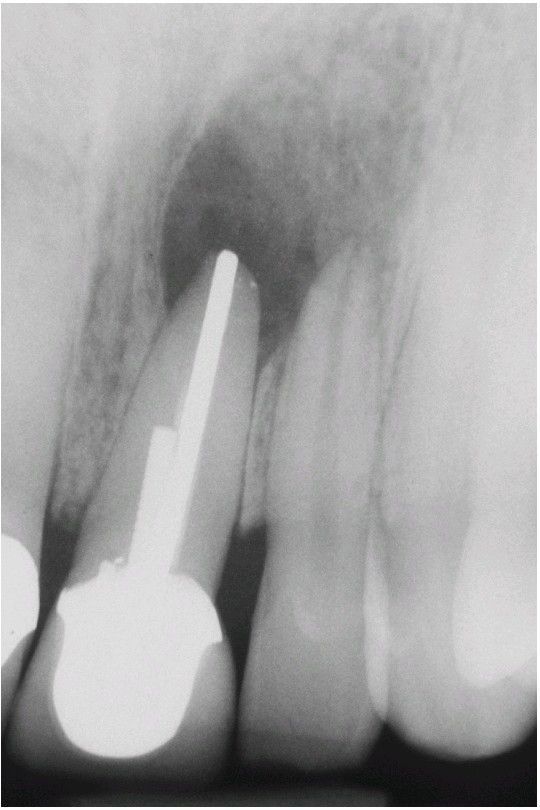

Central Giant Cell Granuloma

. The periapical radiograph shows a radiolucent area involving the apex of an endodontically treated tooth. This was considered preoperatively to represent a periapical granuloma or periapical cyst.